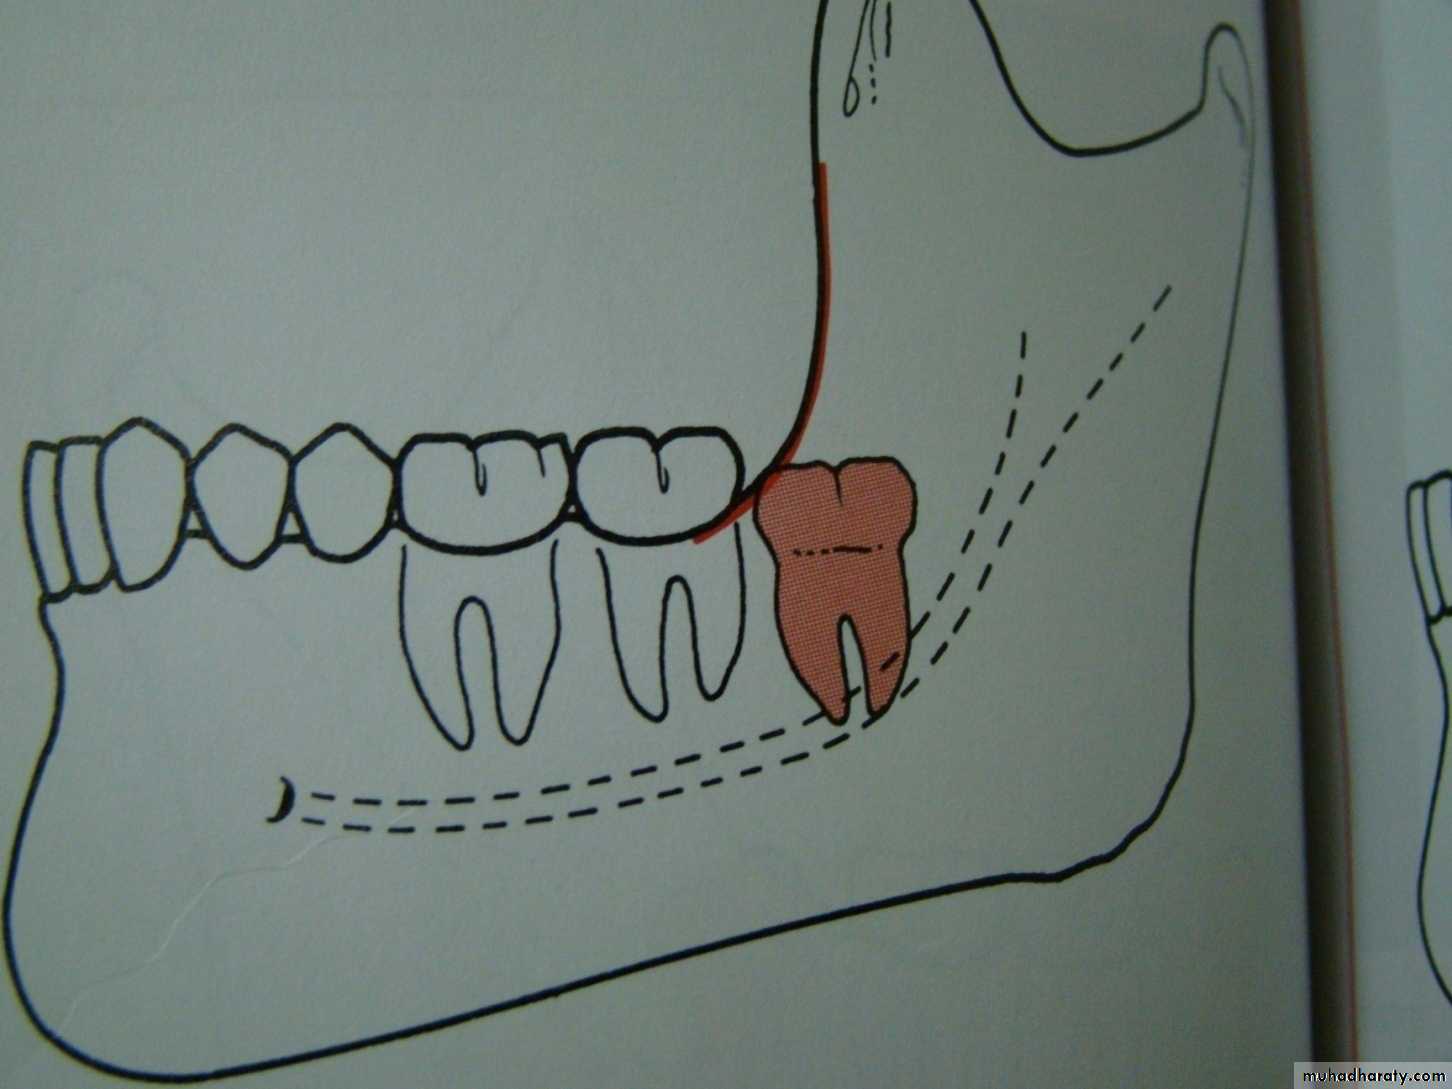

Winters classification of impacted lower third molar

Mesio angularDisto angular

Horizontal

Vertical

Inverted

Transverse

Buccoversion

Linguversion